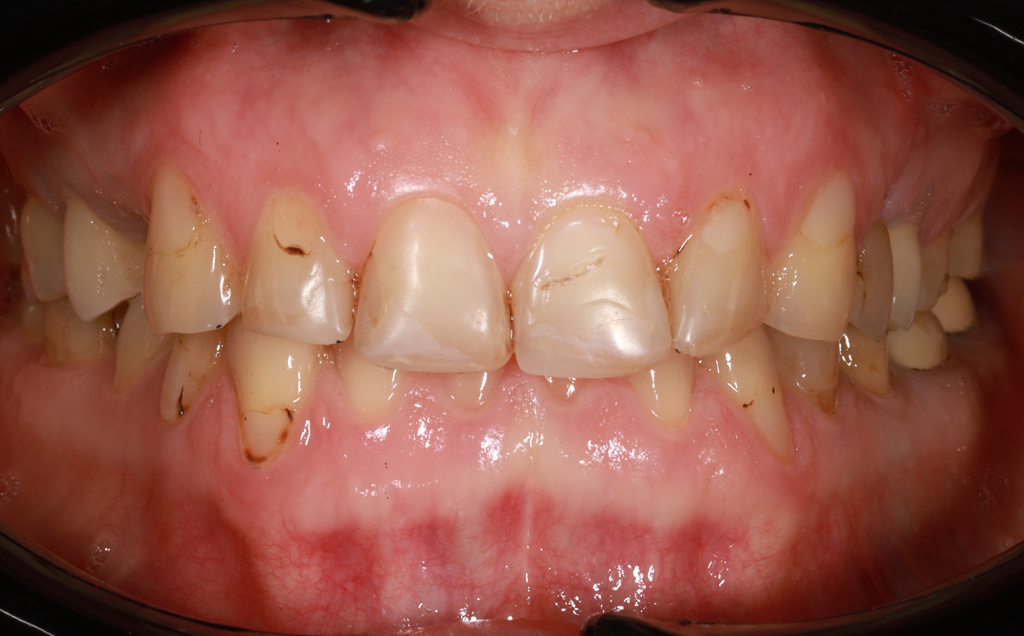

Zaprezentujemy serię poruszających historii pacjentów, którzy zdecydowali się na kompleksowe leczenie dentystyczne. Od przypadków zaawansowanej próchnicy, przez wypadki, które wymagały rekonstrukcji zębów, po pacjentów marzących o hollywoodzkim uśmiechu dzięki zastosowaniu licówek – każda historia jest dowodem na to, jak nowoczesna stomatologia może odmienić życie.